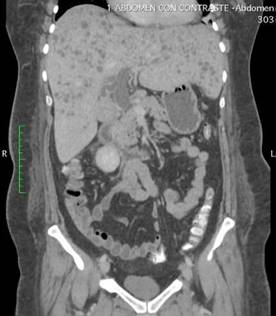

Dentro la evolución del cuadro clínico la paciente presentó una evolución estacionaria, persistiendo con taquicardia, y taquipnea, además de leucocitosis de 19 200 con neutrofolia de 95%, a pesar de haber removido la causa de la obstrucción (coledocolitiasis) y haberse administrado antibióticos (ceftriaxona 1 g EV cada 12 horas y metronidazol 500 mg EV cada 8 horas) durante 72 horas. Es así, que se realiza nueva ecografía abdominal (Figura 2) la cual reportó: “microabscesos hepaticos?, dilatación de vía biliar extrahepática hasta 18 mm y vesícula con barro biliar”, por lo que tras ser valorada por el servicio de medicina interna se decide realizar tomografía axial computarizada (TAC) de abdomen con contraste y en el contexto de una sepsis de foco abdominal por probables microabscesos hepáticos se decide rotar el esquema de tratamiento antibiótico a meropenem 1 g EV cada 8 horas, descontinuando ceftriaxona, y continuando metronidazol 500 mg EV cada 8 horas. En misma fecha se realiza TAC de abdomen con contraste (Figura 3 y 4) la cual reporta: “hepatomegalia, innumerables microabscesos hepáticos, dilatación de vía biliar intra y extrahepatica, a descartar engrosamiento de la pared lateral izquierda de la vesícula biliar, ganglios periportales de etiología por determinar (origen inflamatorio vs metastásico) y mínimo derrame pleural bilateral”. Posteriormente, se solicitan marcadores tumorales de CA 19.9, CA 125, AFP y CEA, todos ellos con resultados dentro de parámetros normales.

Fuente: examen de la paciente realizado en centro de imagen extrainstitucional.

Figura 4. Tomografía axial computarizada de abdomen con contraste (corte axial) que evidencia la presencia de múltiples microabscesos distribuidos en ambos lóbulos hepáticos.